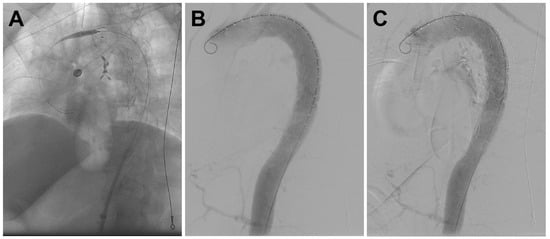

2. Case Report